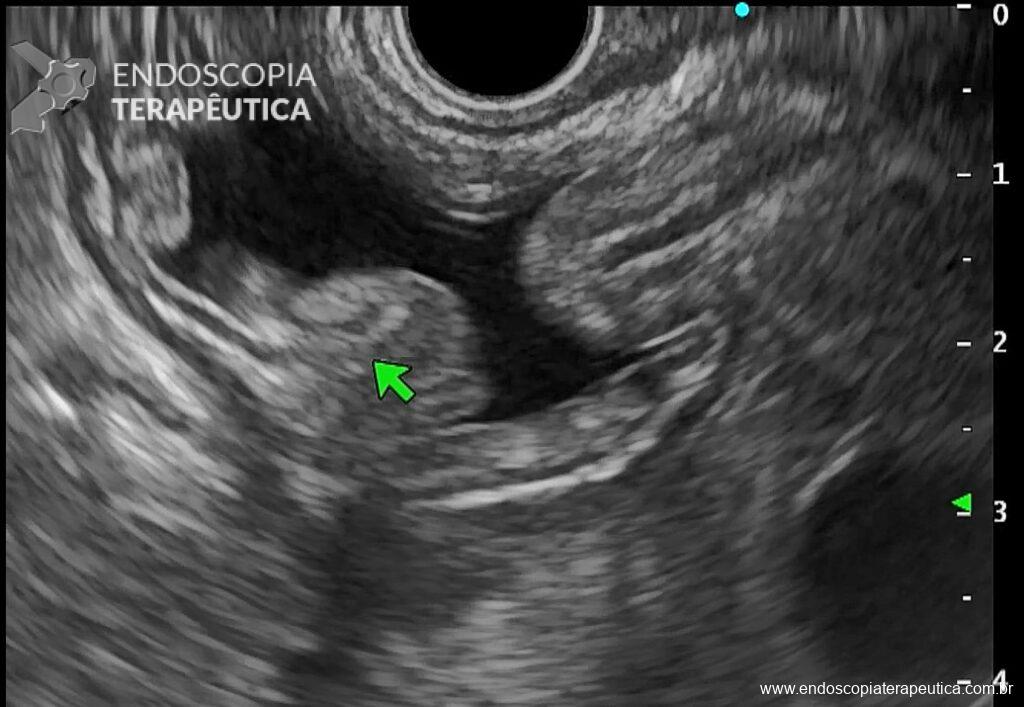

Passo 1: Avaliação ecoendoscópica

- Em transição esofagogástrica, localizar a borda inferior do fígado e girar sentido horário pela visão ecoendoscópica até localizar a “bolacha do mar”, sand dollar sign, que seria o estômago excluso em sua porção antral (Figura 2);